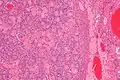

| Micrograph of a sex cord tumour with annular tubules. H&E stain. | |

It has a distinctive appearance under the microscope, from which it derives its name.